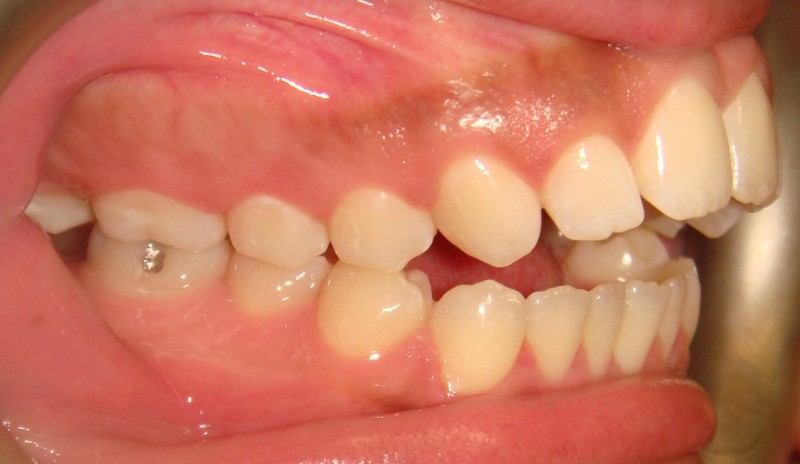

Pretreatment - Patient on Presentation